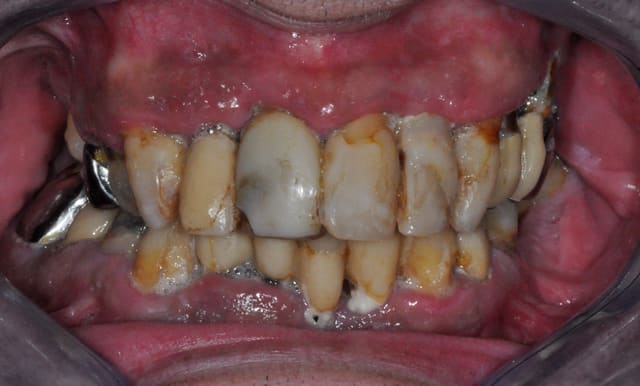

sans avoir l'intention de me moquer, parce que chacun rencontre ses propres difficultés au quotidien, je vous propose d'envoyer vos meilleurs photos de bouche la plus dégueu que vous ayez rencontré.

je commence:

vu ce matin (j'ai encore la nausée, l'odeur est tenace, même avec les fenêtres ouvertes)...

l'assistante; de quand date votre dernier rdv ?

" ho! ça fait un bail, mais comme je n'ai aucun problème je ne viens pas"

moi; et mis à part cette petite douleur qui vous empèche de dormir depuis trois jours, tout va bien ?

" oui, c'est parfait"